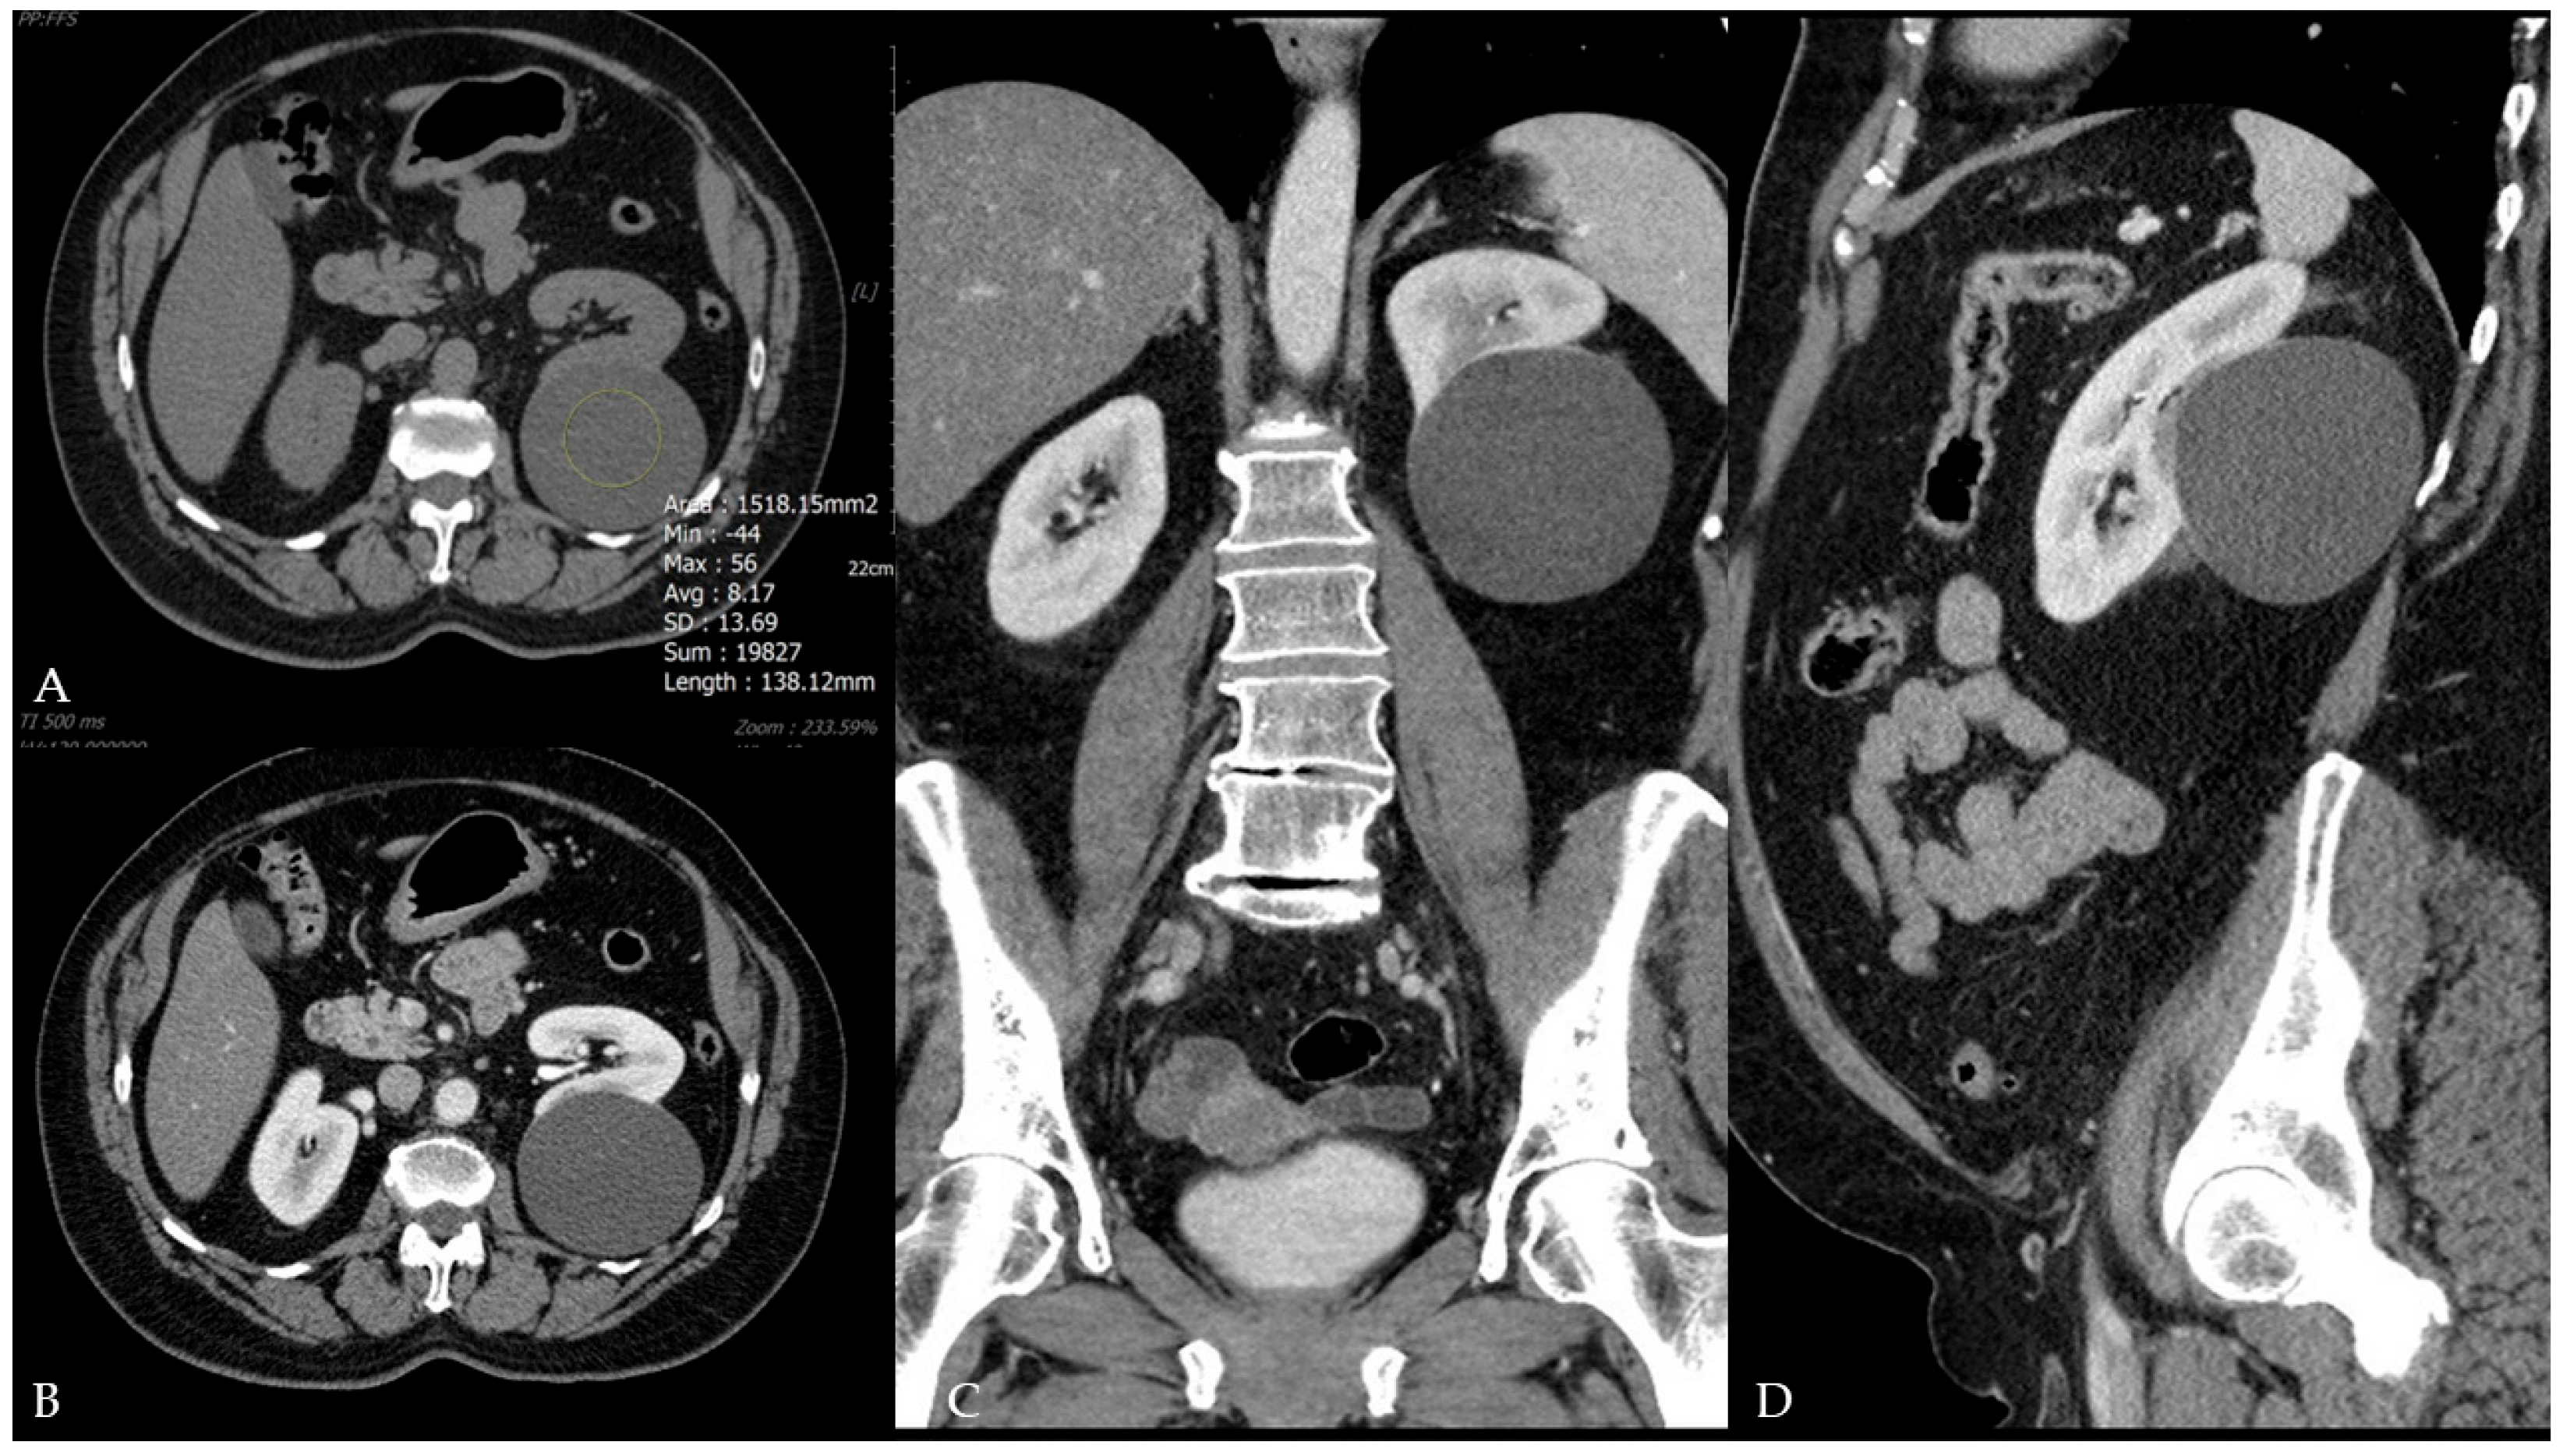

Malignant Transformation of Renal Cyst with Bosniak I Features

Ćulap, S.; Brkić, F.; Matković, A.; Svetec, J.; Jurjević, N.; Horvat Pavlov, K.; Vidjak, V.; Ferenc, T. Malignant Transformation of Renal Cyst with Bosniak I Features. Diagnostics 2025, 15, 1326. https://doi.org/10.3390/diagnostics15111326